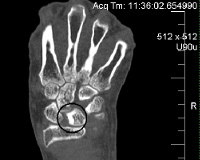

КТ кисти

Процедура назначается при переломах рук различной этиологии, включая старческий и остеопороз, при тяжелых тяжелых травмах, связанных с повреждением окружающих тканей. Манипуляции также используются для контроля состояния фрагментов после операции или сокращения и для оценки развивающегося каллуса во время лечения. КТ кисти необходима в случаях подозрения на новообразование кости и хряща верхней конечности для уточнения местоположения патологического очага, его распространенности и вовлечения окружающих тканей. Процедура рекомендуется для выявления вывихов, повреждения кистей, аномального развития структур кости или хряща, диагностики артрита, остеоартрита, подагры и остеопороза. КТ показана при подготовке к операции, чтобы контролировать динамику заболевания, уточнить результаты рентгенологического и других исследований.